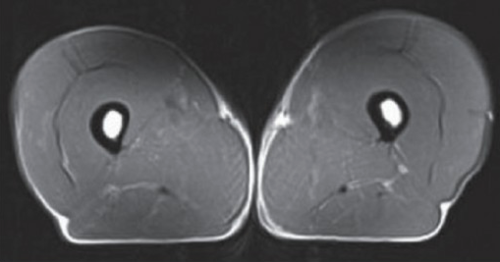

Compare this with a 74 year old sedentary man:

Not much muscles left in those thighs.